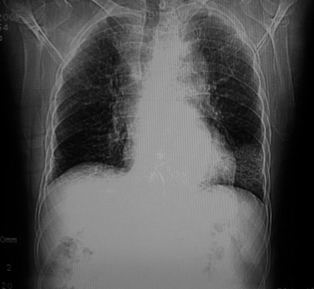

男,78岁,咳嗽、咳痰、发热入院,抗炎治疗一周后已退热,咳血似痰。

10月3日片: